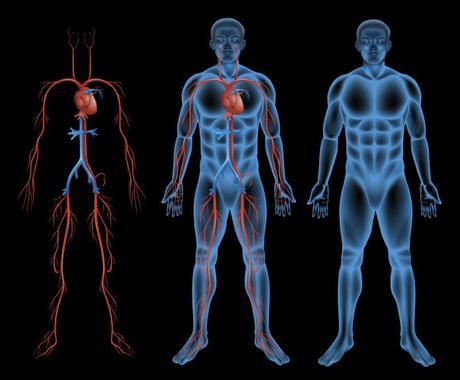

Tener una correcta circulación sanguínea permite al cuerpo mantener los músculos en óptimo funcionamiento, practicar un ejercicio de alta intensidad también puede hacer que las piernas se hinchen y la circulación sanguínea sea restringida.

La circulación sanguínea tiene un objetivo principal que es trasportar el oxígeno y algunos minerales a cualquier célula de nuestro cuerpo, esta es comandada por nuestro corazón que bombea cada segundo.